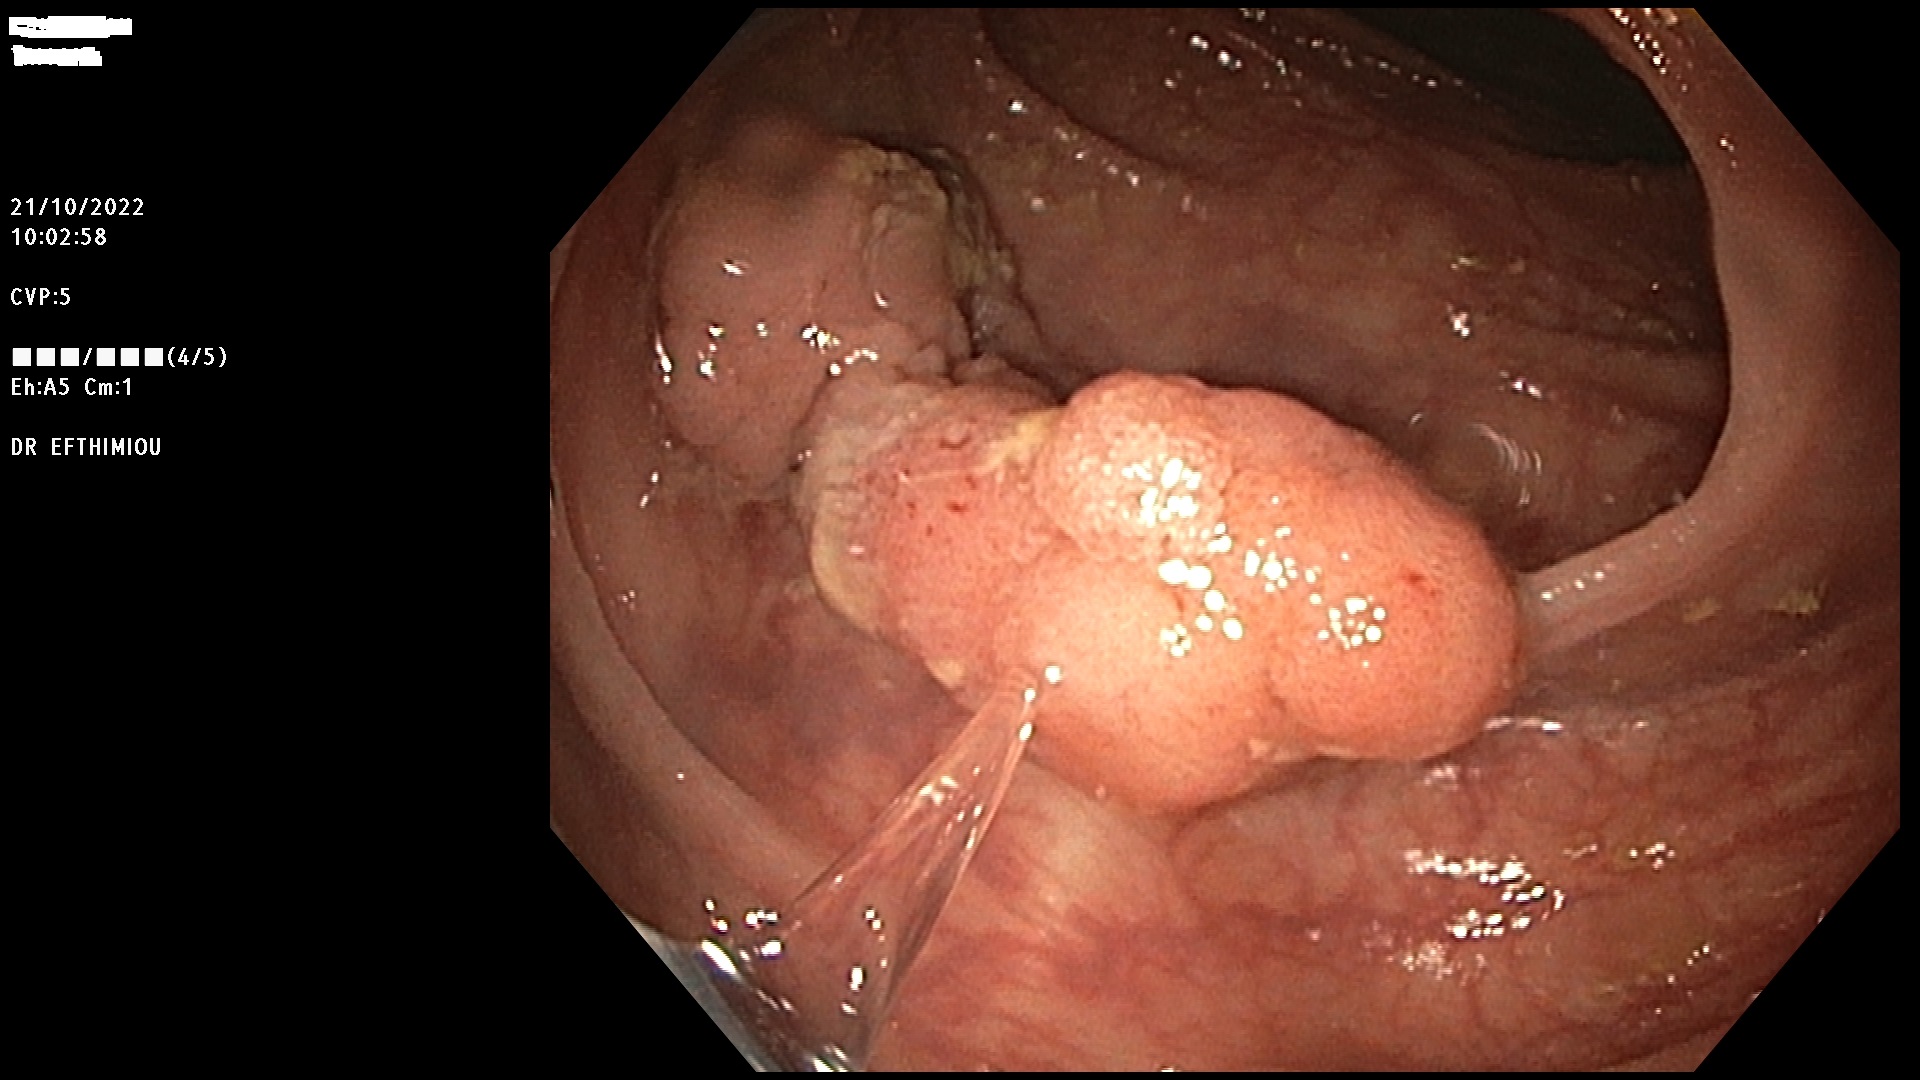

Η επέμβαση γίνεται κατά τη διάρκεια της κολονοσκόπησης με τη χρήση

διαφόρων εργαλείων (λαβίδες, βελόνες υποβλεννογόνιας έγχυσης, βρόχοι

διαθερμίας, ψυχροί βρόχοι, endoloops, κ.ά.) ανάλογα με το μέγεθος, τη

μορφολογία και την εντόπιση του πολύποδα (Εικόνες 1-3). Ο ασθενής

βρίσκεται σε ήπια καταστολή («μέθη») και δεν αισθάνεται καθόλου πόνο.